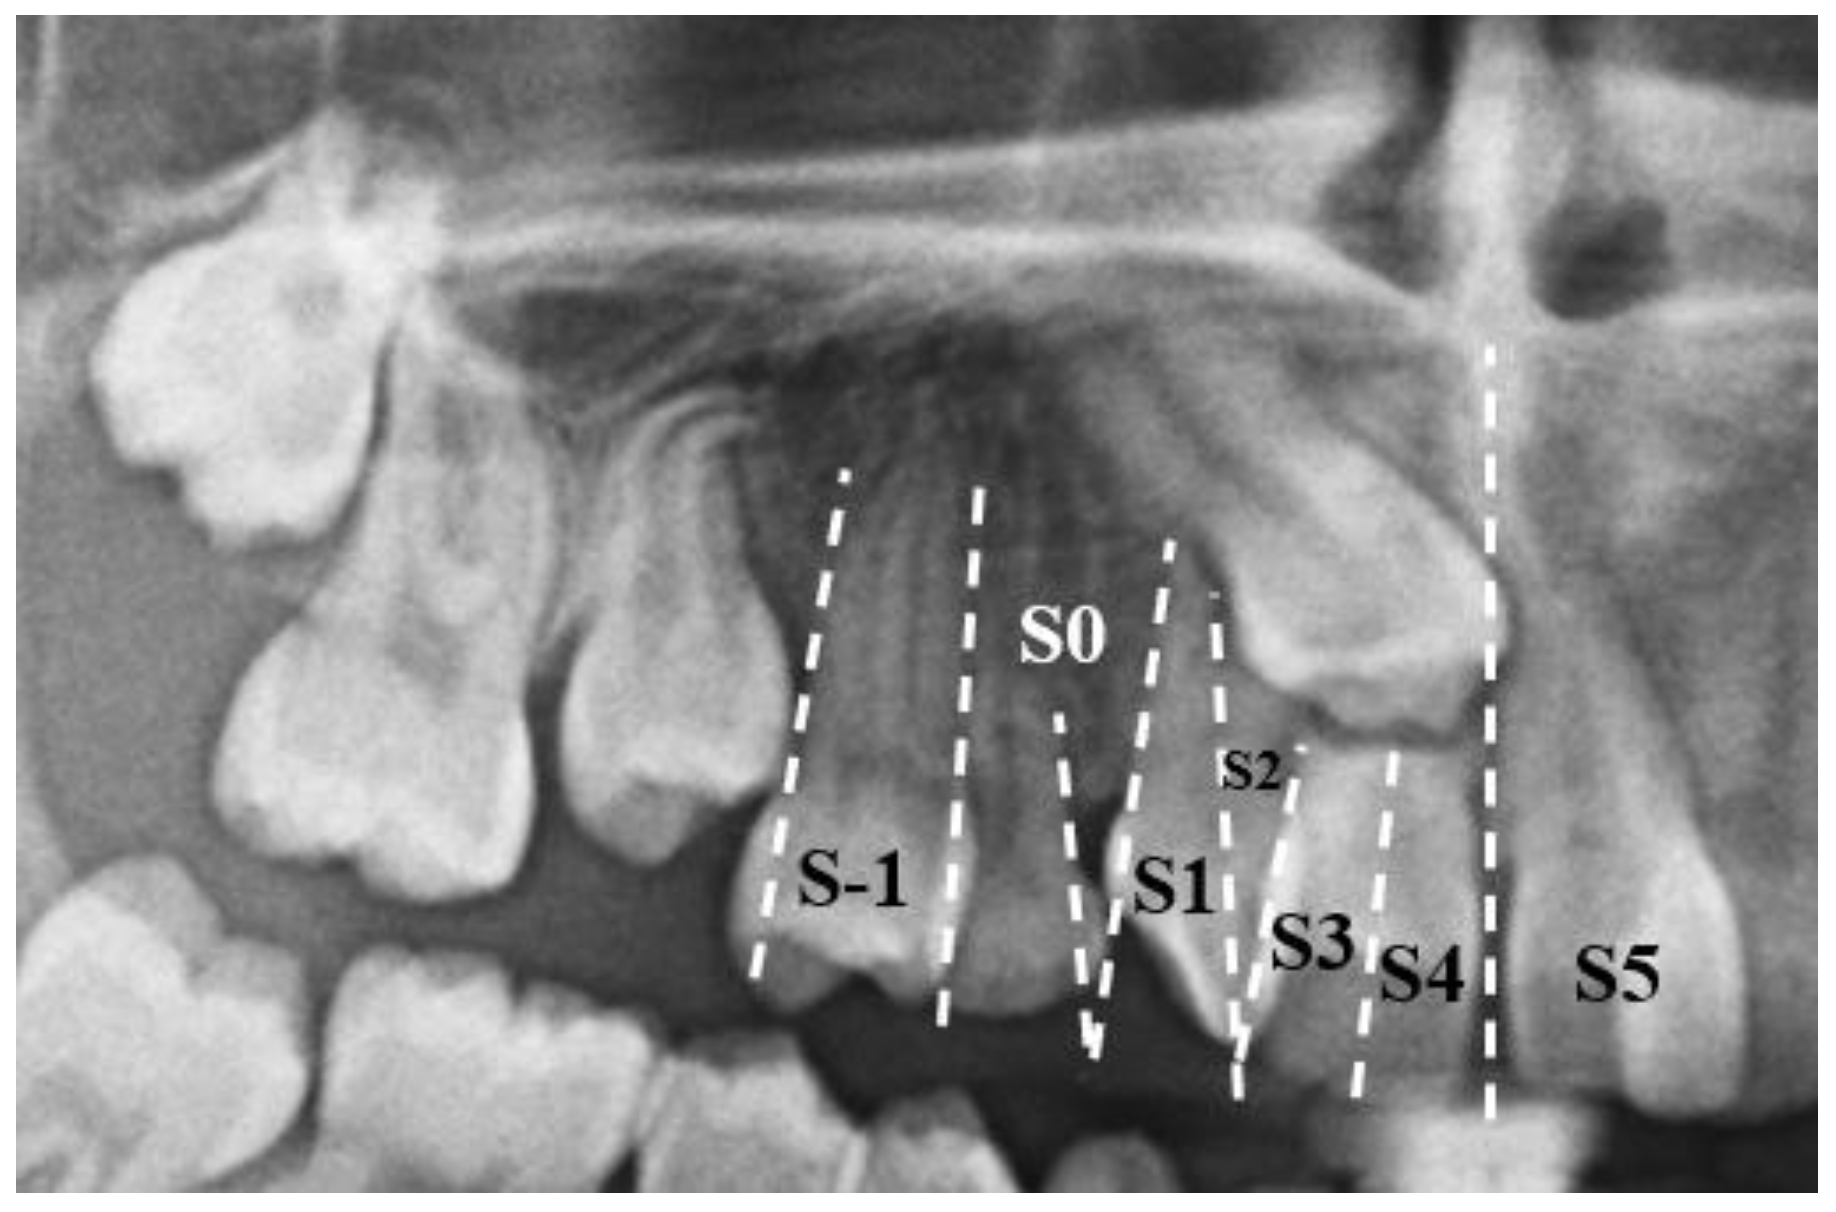

2.7. Clinical Case

| Pinho T., Amaral R. 2025 | ♀ 13 YO | Mx.C.I1 | C | R | V (impacted) | Cl I | Maintained | -Total root resorption of tooth #11 due to the position of the ectopic canine |

3.2. Clinical Case